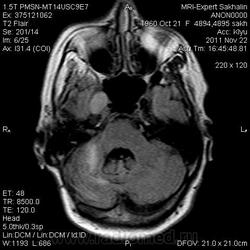

Петро-кливальная менингиома-рецидив?

Женщина по направлению нейрохирурга.В мае 2011  года оперирована по поводу петро-кливальной менингиомы ( где конкретно-слева или справа-история умалчивает, предыдущие исследования и описания не представила).Кроме менингиомы  нашла еще несколько изменений в головном мозге.Хочу послушать мнение уважаемых коллег и сравнить со своими умозаключениями.Это для самоконтроля-честное слово!

Постконтраст.

Спасибо за посты.А расширение базальных цистерн и широкое сообщение с 4 желудочком?

Состояние после провденного оперативного лечения в ЗЧЯ (кистозно-глиозные изменения в правом полушарии мозжечка, послеоперационный костный дефект затылочной кости справа). Объемное образование медиобазальных отделов правой височной области (параселлярно справа). Хорошо копит контраст. Возможно - рецидив, возможно остаточный фрагмент или продолженный рост... Надо знать что было до операции... Не вижу "кливального" компонента... Не исключено распространение в проекцию основной пазухи (по моему как минимум деформирована ее стенка).

Еще не нравится что "копит" намет парасагитально справа, но толком не рассмотреть...